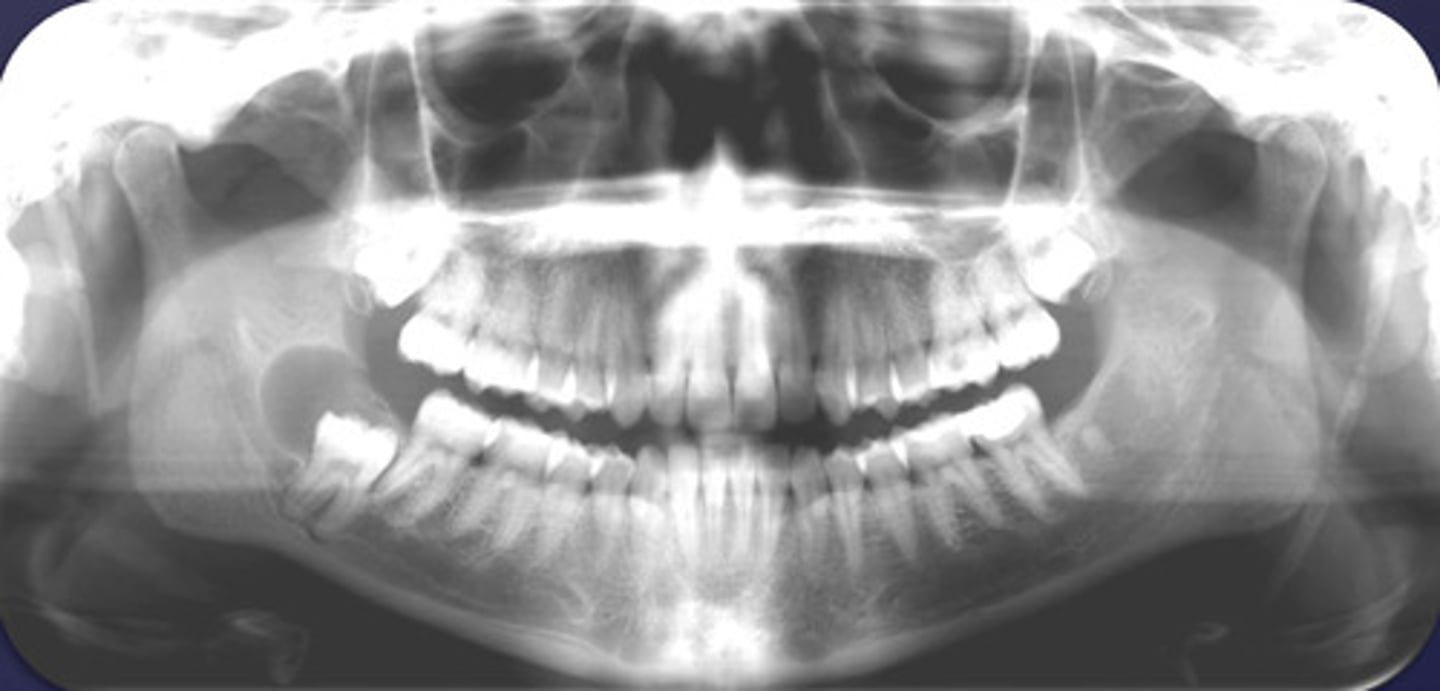

how would you describe this lesion? (not the giant cavity btw)

A. defined, corticated, periapical radiolucency causing loss of lamina dura and PDL space on #6-7

B. defined, non-corticated, periapical radiolucency causing loss of lamina dura and PDL space on #6-7

C. ill-defined, circular radiolucency located above tooth #7

D. well-defined, corticated, radiopacity

- Also note epicenter located above apex # 7 which has large dental caries.

What category would this lesion be part of?

Inflammation/benign

all of the following could be a differential diagnosis for the following lesion EXCEPT?

A. radicular cyst

B. Periapical granuloma

C. apical rarefying osteitis

D. renal osteodystrophy

what category would this lesion be classified into?

inflammatory/benign cystic